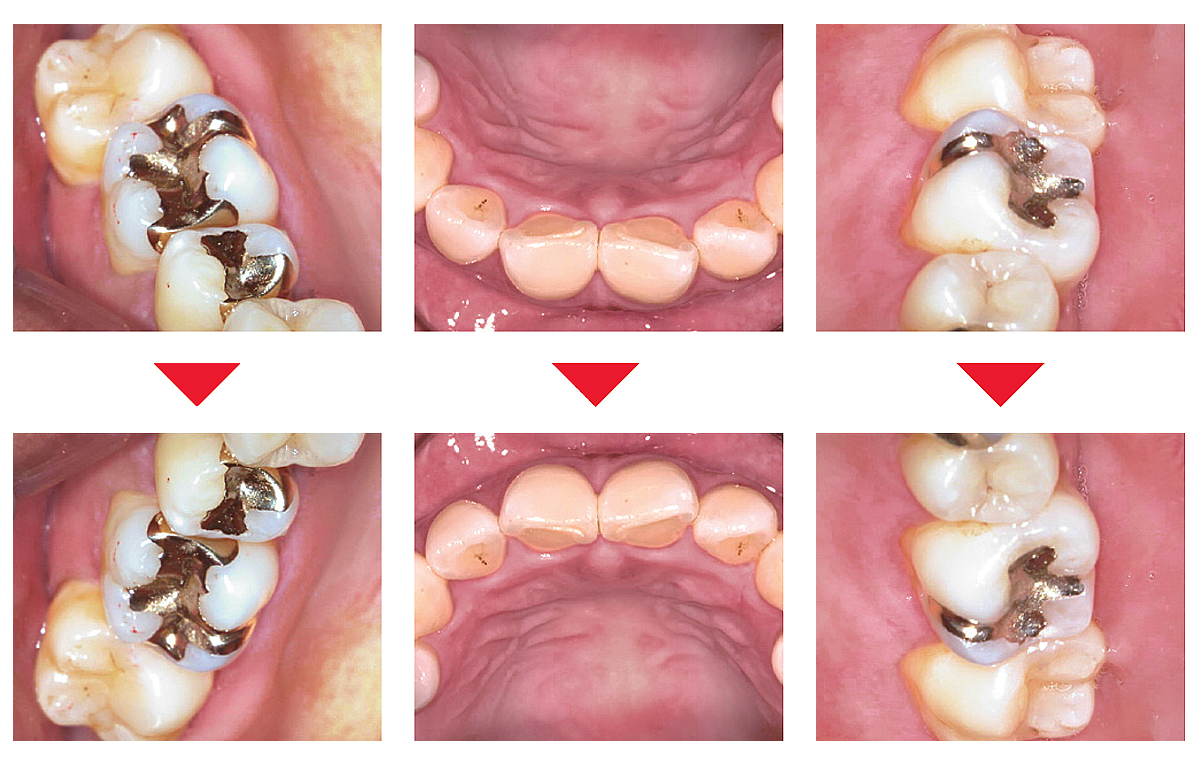

映像の上下左右をワンタッチで反転でき、術者だけでなく患者さんにも伝わりやすい向きで表示できます。5枚法や9枚法の撮影にも便利です。

▶口腔内写真の撮影方法はこちら